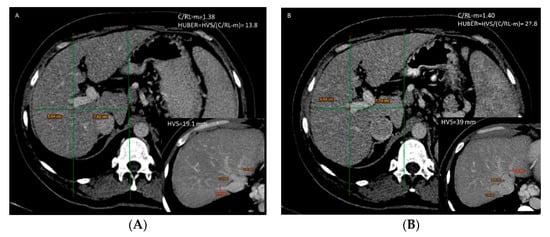

3.4. Huber’s Score

3.5. Liver Volume

| Huber’s score | 19.16 | 11.50 | 20.58 | 9.73 | 0.035 |